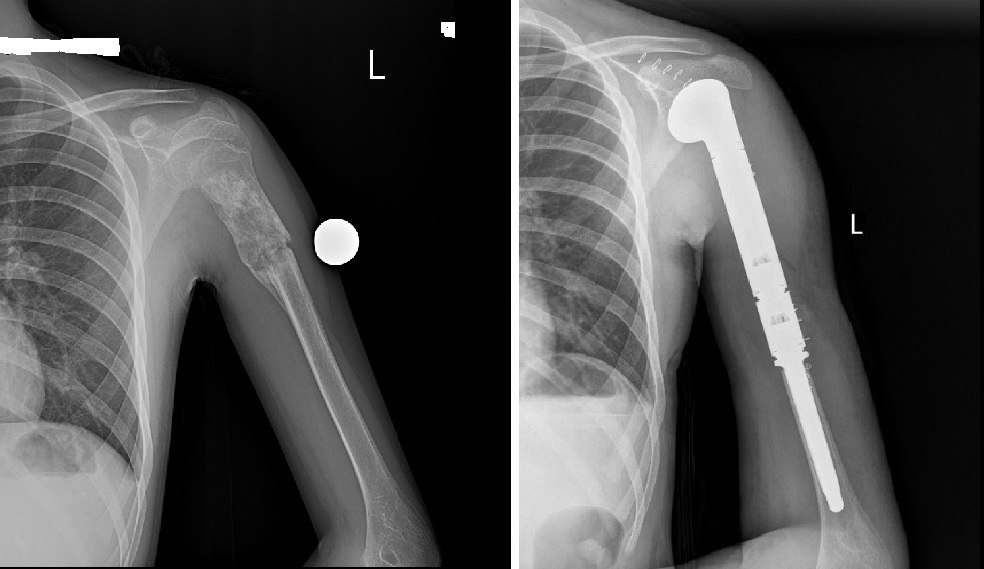

Улсын нэгдүгээр төв эмнэлгийн ХҮСҮСТ-ийн дарга М.Отгонбаяраар ахлуулсан үений мэс заслын баг Монгол Улсад анх удаа атгаал ясны дээд хэсгийн гуравны хоёрыг хамарсан том хэмжээний ясны хортой (osteosarcoma) хавдрын тохиолдолд хавдрыг бүхэлд нь авч мега-протез суулгах мэс заслыг амжилттай хийж гүйцэтгэлээ.

Ясны хавдрын үед том хэмжээний имплант суулгах мэс заслыг анх 2015 оноос эхлэн доод мөчдөд хийж эхэлсэн ба энэ удаагийнх нь дээд мөчид хийсэн анхны тохиолдол юм. Энэхүү мэс заслыг хийснээр хэд хэдэн давуу талтай. Тухайлбал, мөчийг тайрахгүй хадгалж үлдэх, хөл, гар, мөчдийн үйл ажиллагаа эргэн сайжрах, эх орондоо эмчлэгдэх боломжтой болж, гадагш явах санхүүгийн дарамтаас чөлөөлөгдөнө. Уг эмчилгээний тохиолдлын мега-протез нь тухайн хүн өсөж томроход сунгагдах боломжтой тул дахин солих шаардлагагүй юм.